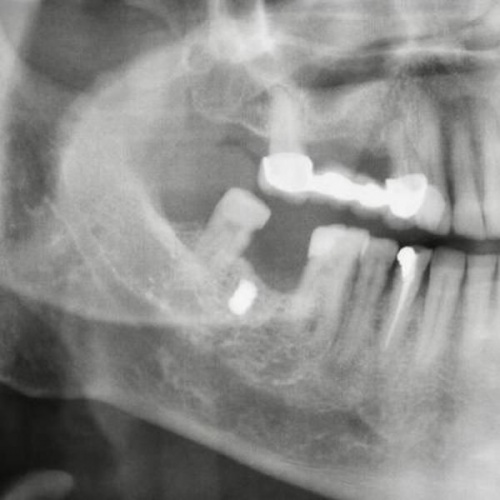

Akın'ı muayene ettikten sonra çekilen röntgen filmini inceleyen Dr. Öğretim Üyesi Yakup Gülnahar, yanağında bir parça olduğunu belirledi. Muayenede 15 yıl önce yaşadığı bir olayı hatırlayan Akın, benzinli hızar ile odun kestiği sırada zincirin koptuğunu ve daha sonra yanağında şişlik oluştuğunu söyledi.

Dr. Gülnahar'ın mıknatıs ile yaptığı kontrolde parçanın metal olduğu tespit edildi. Dr. Gülnahar, ameliyat ile Akın'ın yanağındaki metal zincir parçasını aldı.

Diş tedavisine gelince metal parçanın röntgen ile görüldüğünü belirten Faik Akın "Dr. Öğretim Üyesi Yakup Gülnahar, ağzımdaki şişliğin implant parçası olup, olmadığını sordu. Ben de kendisine implant yaptırmadığımı söyledim. Sonra aklıma 15 yıl önce yaşadığım hızar kazası geldi ve doktora anlattım. Yakup bey, mıknatıs ile kontrolü sonrası yanağımdaki parçanın metal olduğunu belirledi.

u200bDr. Öğretim Üyesi Yakup Gülnahar da "Faik bey, rutin diş tedavisi için bize geldi. İstenilen röntgen filminde bir cisme denk geldik. Kendisine 'İmplant yaptırdınız mı?' diye sordum. 'Hayır' dedi. Bu sefer, hasta geçmişinde yaşadığı bir kazadan bahsetti. Kontrol ettiğimiz de mıknatısın şişliği çektiğini gördük. Başarılı bir operasyon ile demir parçasını aldık. Hasta şu anda gayet iyi" diye konuştu.